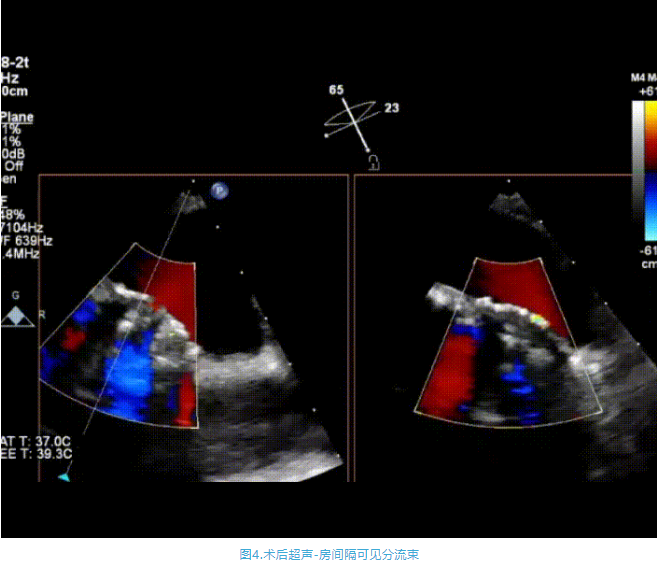

術(shù)中首先在局麻下穿刺股動脈、股靜脈,完成心導(dǎo)管檢查評估后轉(zhuǎn)為全麻,在食道超聲引導(dǎo)下穿刺房間隔,穿刺成功后將加硬導(dǎo)絲送入左上肺靜脈建立軌道,根據(jù)患者病情行球囊預(yù)擴(kuò)張后植入6mm孔徑房間隔造孔支架,經(jīng)透視及食道超聲評估支架左右盤展開良好,夾持于房間隔兩側(cè),固定穩(wěn)定、位置良好,食道彩超顯示房水平右向左為主分流,分流孔直徑符合預(yù)期大小,心導(dǎo)管檢查評估達(dá)到預(yù)期效果,釋放造孔支架。術(shù)后12h患者下床活動,恢復(fù)順利,擬于近日完善術(shù)后評估后出院。